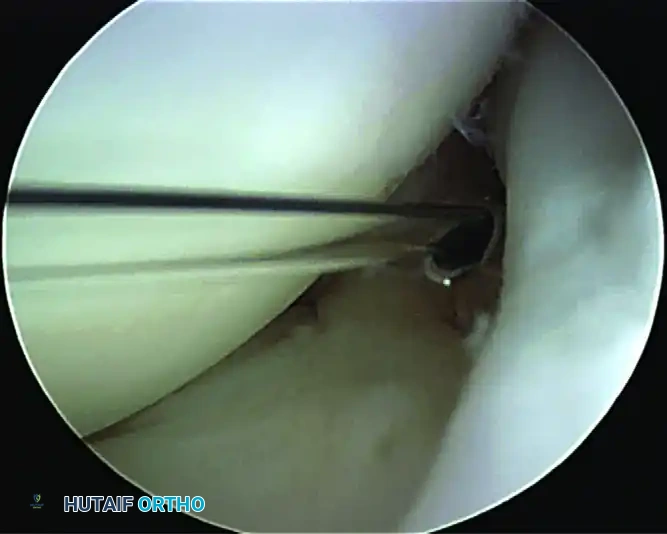

The Dynamic Peel-Back Test

The peel-back test, as described by Burkhart, is the definitive dynamic maneuver to evaluate for a posterior-dominant Type II SLAP lesion.

To perform the peel-back test:

1. Remove the operative arm from the traction suspension.

2. Observe the superior labrum arthroscopically from the posterior portal.

3. Have an unscrubbed assistant carefully bring the arm into 90 degrees of abduction and 90 degrees of external rotation (the late cocking position).

Arthroscopic view of a positive dynamic peel-back test demonstrating the medial displacement of the biceps-labral complex.

Performing this dynamic maneuver in a shoulder with a posterior SLAP lesion causes the entire biceps-superior labrum complex to drop medially over the edge of the glenoid.

Clinical Pearl: The positive peel-back sign is highly diagnostic for a posterior SLAP lesion. However, isolated anterior SLAP lesions often have a negative peel-back test. In these cases, rely on the probe assessment, sulcus depth, and the presence of granulation tissue.